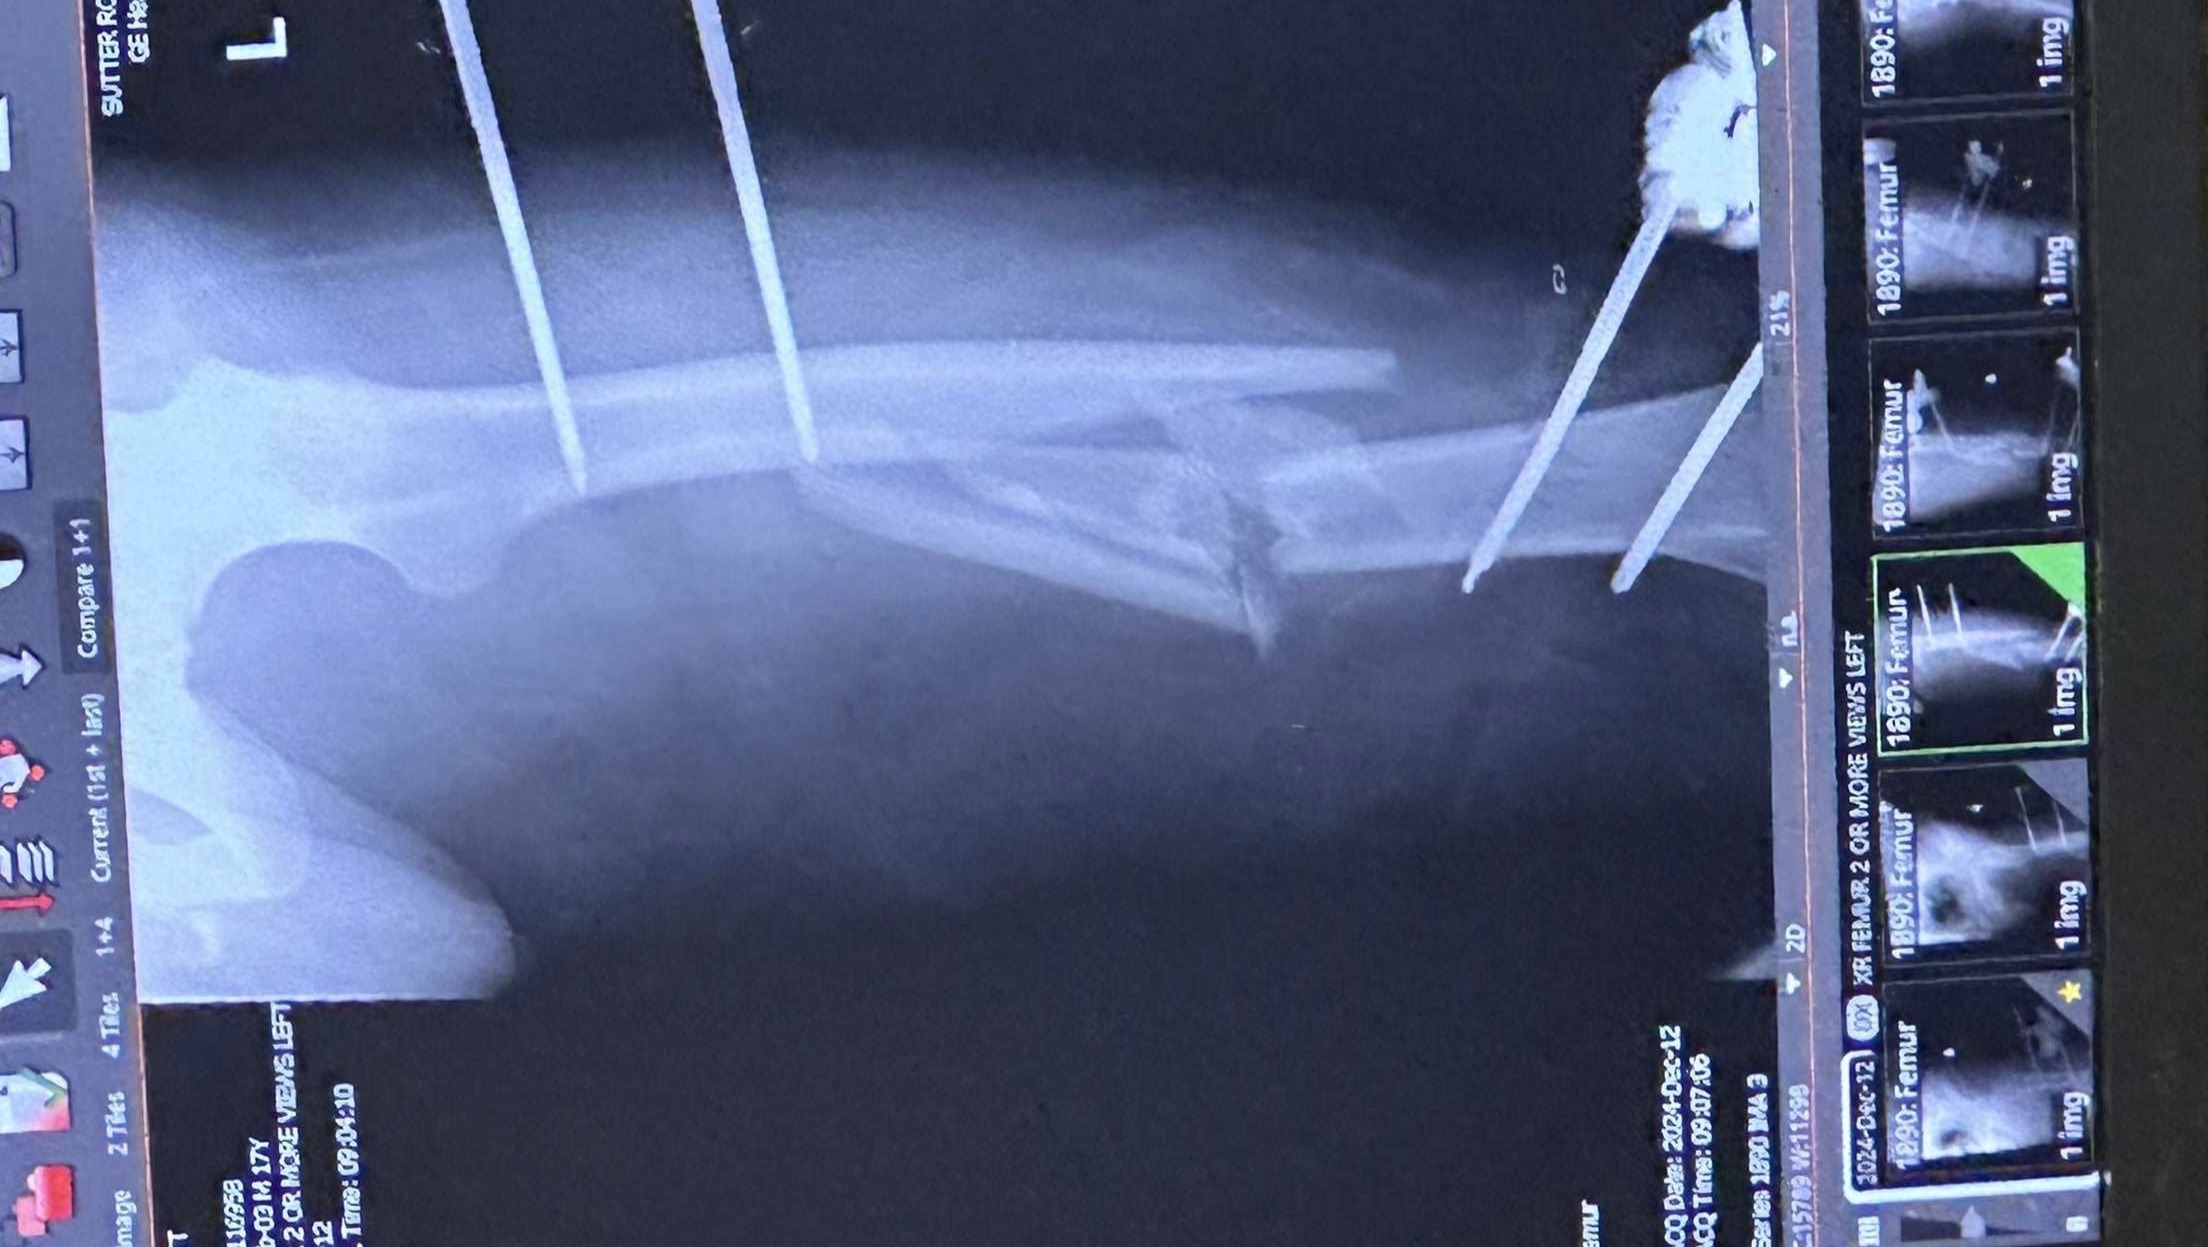

Hi, I'm Paul Koenig, a family friend of Matt Ward, who was in a serious motorcycle accident, being hit by a minivan. He's currently laid up in the hospital with a broken leg and has undergone two major surgeries for limb salvage/reconstruction. Matt still has numerous upcoming surgeries to save and rebuild his left leg. He's asking for donations to help with impending medical expenses. He's due to graduate from high school this year and was enrolled in trade school starting in July to become an automotive mechanic. With this accident, those plans might be delayed, and he needs help to get through this challenging time.